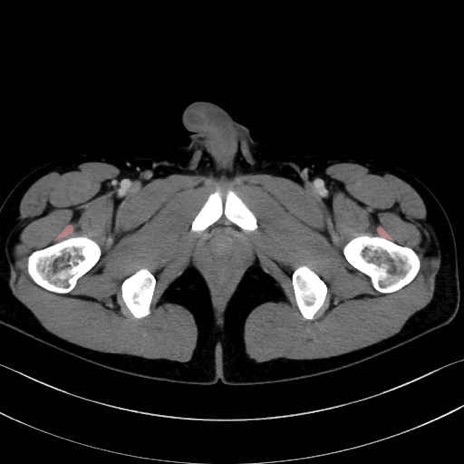

中間広筋 (Vastus intermedius)